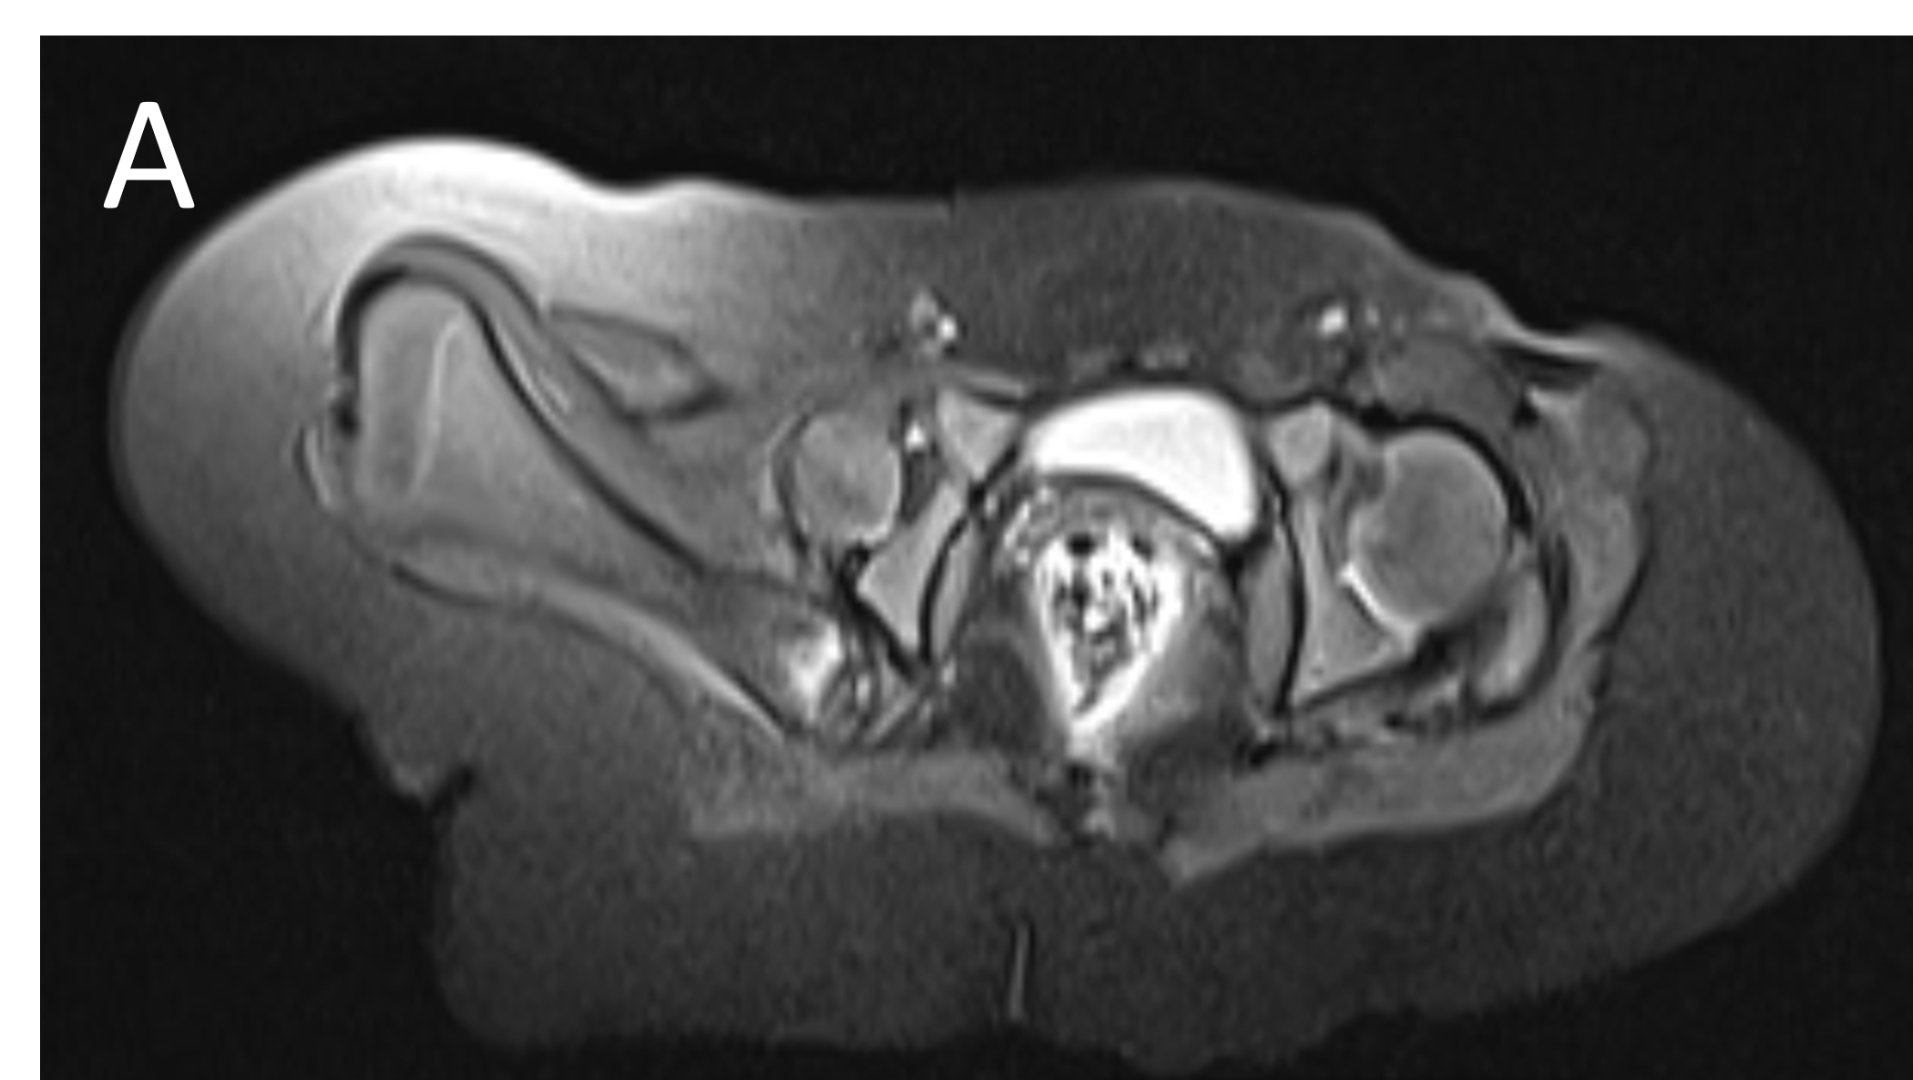

- A.FINDINGS – MR BILATERAL HIPS

- A.LEGENDS – MR BILATERAL HIPS :Right femur is shortened, with a coxa vara deformity. Femoral shaft measures 7.2 cm in length. The acetabulum is moderately dysplastic and anteriorly rotated, But contains the femoral head. The femoral head and neck appear hypoplastic and posteriorly and externally rotated.